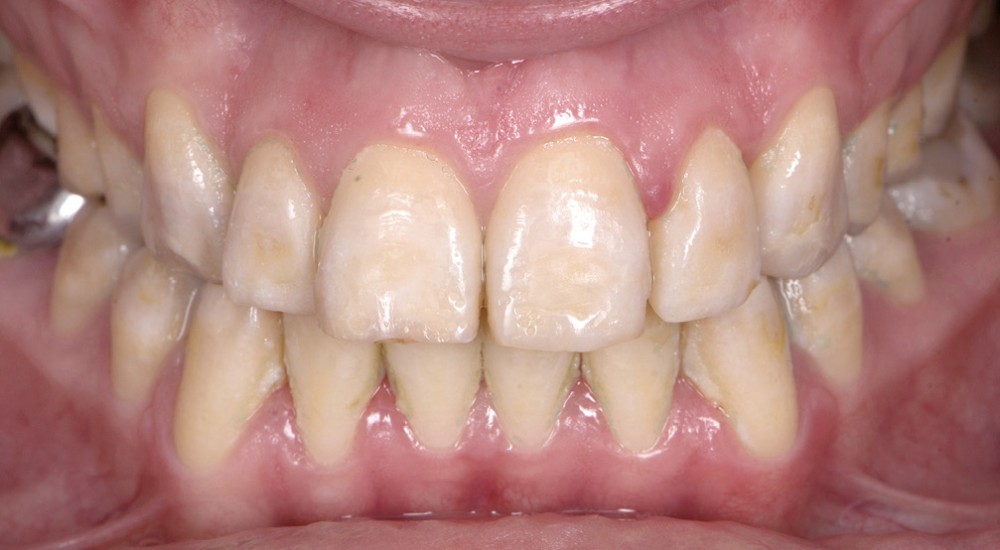

Dans tous les cas, le préjudice de l’enfant ou de l’adulte est non seulement fonctionnel – caractérisé par des sensibilités dentaires plus ou moins accrues, des malpositions occlusales associées parfois à une perte de dimension verticale – mais aussi esthétique, par l’aspect plus ou moins coloré et malformé des dents (fig. 1a, b). Le retentissement psychologique est variable selon la sévérité de l’atteinte et l’environnement social, mais reste important, surtout dans l’enfance [3].